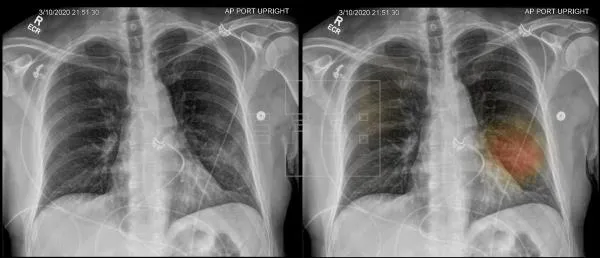

Publicaron en The Scientist un reporte de un interesante y reciente proyecto, en donde narran cómo un grupo de investigadores chinos logró entrenar a una inteligencia artificial para diagnosticar Coronavirus Covid-19 a partir del análisis de radiografías pulmonares.

La clave de todo fue detectar patrones parecidos a un vidrio roto, específicamente según relata el artículo: "Lo más llamativo son los patrones de lesiones turbias que se asemejan a fragmentos de vidrio o líneas reticulares dentro de las lesiones opacas que parecen baldosas irregulares, que se producen alrededor de las periferias de ambos pulmones."

Para esto el software detrás de la IA tuvo que ser entrenada con unas 532.000 fotografías de pulmones, logrando así detectar los casos con efectividad de un 85%.